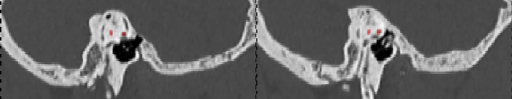

To verify the effectiveness of our proposed method, we conduct ablation experiments to evaluate the 3D dilated convolution module and the multi pooling module. We designed 4 experiments in this section. Firstly, our previous work, 3D-DSD, was used as a benchmark. Secondly, we replace the last dense connection module (called 3D-DCM) in the encoding stage of 3D-DSD with our dilated convolution module. Thirdly, replace the pooling module in 3D-DSD with a multi pooling module(called 3D-MP). Finally, the dilated convolution module and the multi pooling module are simultaneously introduced in 3D-DSD, namely our proposed 3D-MFF. The segmentation performance of 4 schemes are shown in Table 1. And The visualization results of the ablation experiment are shown in Figure 8. In the segmentation of the LSCs, the segmentation results of the segmentation model often suffer from over-segmentation. The red labels denote the ground-truth, the blue labels, blue labels and yellow labels denote the segmented results of 3D-DCM, 3D-MP and 3D-MFF respectively. It can be seen from the visualization results of the ablation experiment that our proposed method has a good overlap with the ground-truth.

Refer to caption

(a) 3D-DCM

(b) 3D-MP

(c) 3D-MFF

Figure 8: The subjective segmentation results of the 3D-DCM, the 3D-MP and the 3D-MFF. The red labels denote the ground-truth, the blue labels, blue labels and yellow labels denote the segmented results of 3D-DCM, 3D-MP and 3D-MFF respectively. We can see that (a) and (b) apt to over segmented and (c) achieved the test result.